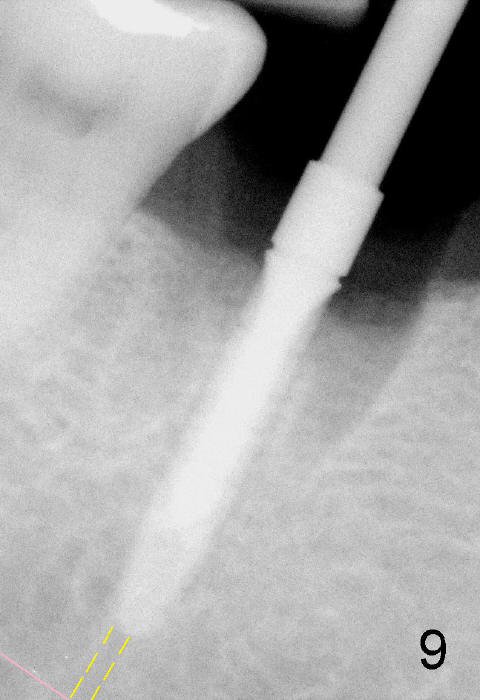

Septal bone is apparently pushed into the mesial and distal sockets (Fig.7 inset arrows) when a small round osteotomes is removed. The deeper portion of osteotomy is created by drills (Fig.8,9). The septal bone is further pushed mesiodistally as the osteotomy enlarges with combination of drills and osteotomes (Fig.10). A 6x17 mm tapered implant is placed with insertion torque >60 Ncm (Fig.11: I).